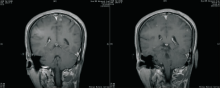

2010-06-21 脑MRI示脑多发转移,见 图4;胸部CT、骨扫描未见肿瘤复发转移。

2010-11-02全脑放疗后复查脑MRI,脑转移瘤全部消失,见 图5。

谢松喜(放疗科副主任医师):非小细胞肺癌脑转移行放疗的情况大致分三种: (1)全脑放疗,适应于多发的脑转移; (2)立体定向放射外科,包括X刀与γ刀,适用于1~2个脑转移瘤;(3)三维适形放疗。EGFR突变的患者,接受脑部放疗加上靶向药物治疗,其中位生存期可达到12个月。我院肿瘤中心目前有一项关于非小细胞肺癌多发脑转移的临床研究,根据患者EGFR突变的情况进行分组:如果患者为腺癌、EGFR没有突变则直接行全脑放疗;如果EGFR突变但既往服用过靶向药物,也接受全脑放疗;如果EGFR突变且既往未服用过靶向药物,则有症状者可选择靶向药物或全脑放疗,无症状者可选择靶向药物治疗。本病例为多发脑转移,且既往已经服用过靶向药物,所以我们选择了全脑放疗。从放疗前后的脑MRI对比来看,患者全脑放疗的效果非常好,脑转移瘤基本消失。